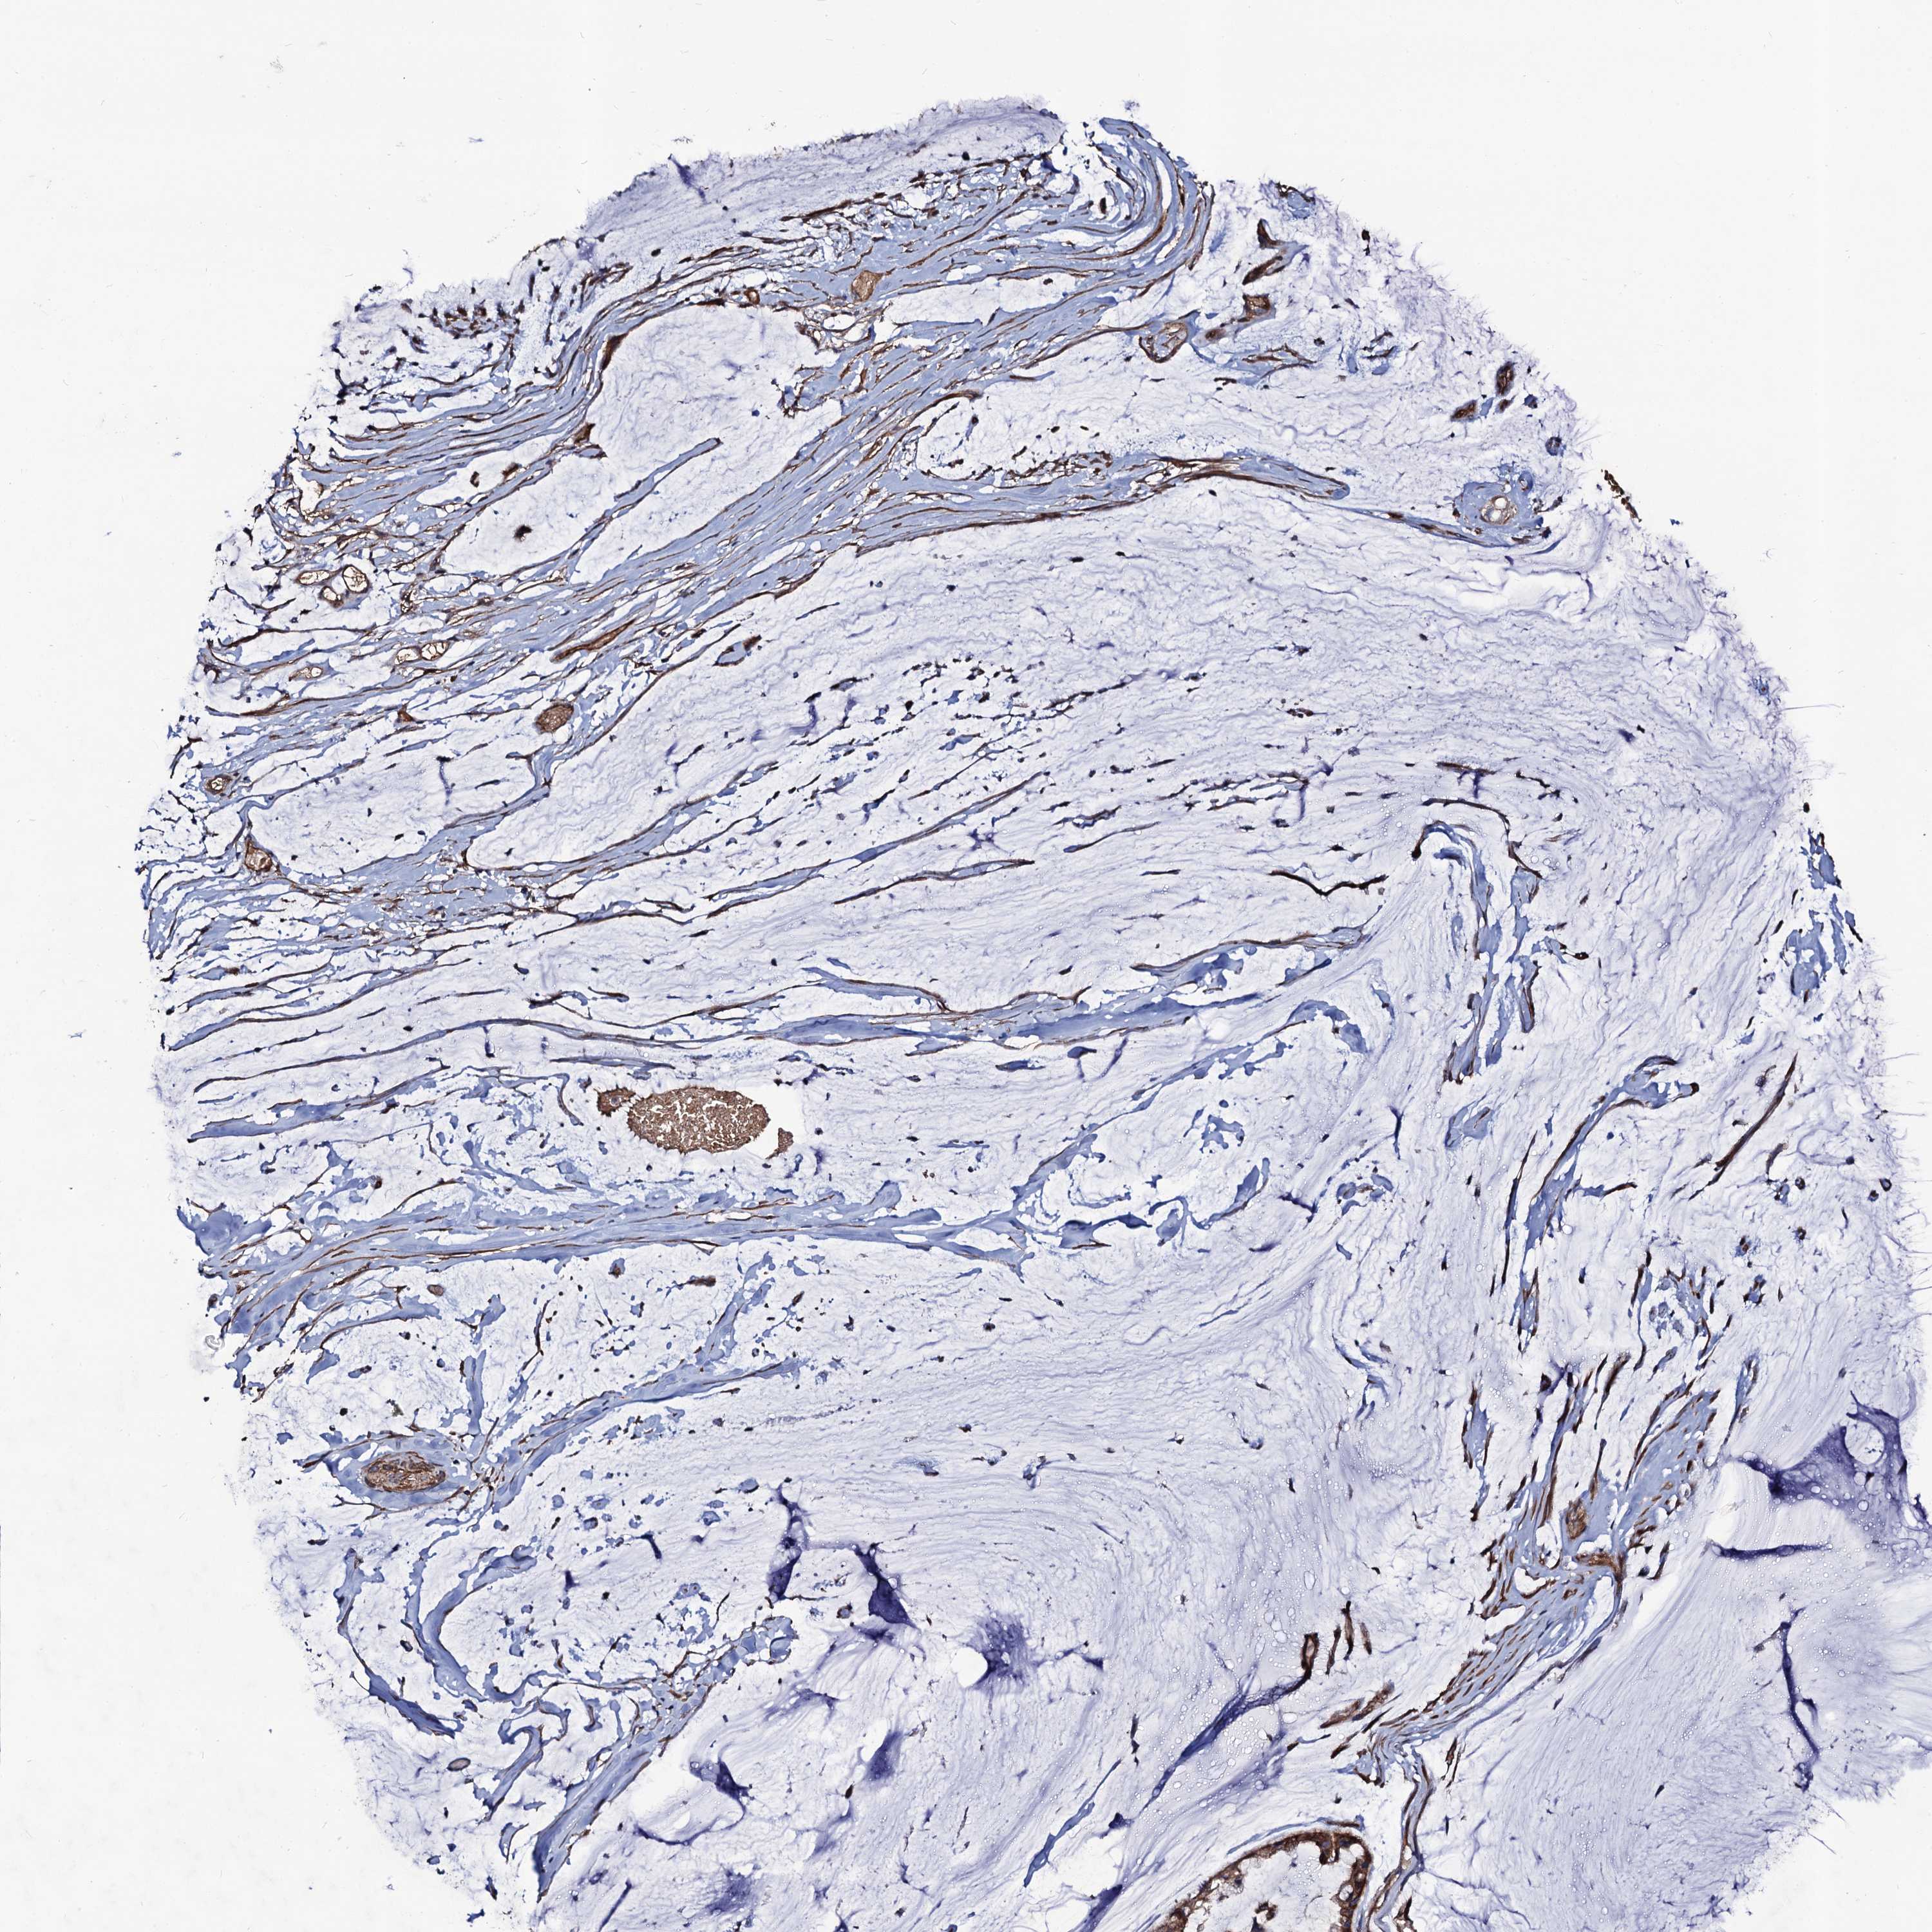

OVARIAN CANCER - Protein expressioni

A mouse-over function shows sample information and annotation data. Click on an image to view it in a full screen mode. Samples can be filtered based on level of antibody staining by selecting one or several of the following categories: high, medium, low and not detected. The assay and annotation is described here.

Note that samples used for immunohistochemistry by the Human Protein Atlas do not correspond to samples in the TCGA dataset.

Antibody stainingi

Antibody staining in the annotated cell types in the current human tissue is reported as not detected, low, medium, or high, based on conventional immunohistochemistry profiling in selected tissues. This score is based on the combination of the staining intensity and fraction of stained cells.

Each image is clickable and will lead to virtual microscopy that enables deeper exploration of all samples and also displays staining intensity scores, fraction scores and subcellular localization as well as patient and tissue information for each sample.

Antibody HPA041507

Antibody HPA041599

Cystadenocarcinoma, serous, NOS